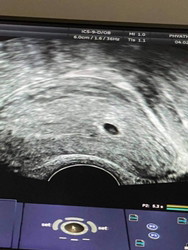

5 สัปดาห์ 6 วัน หัวใจยังไม่เต้นปกติมั้ย?

หลังจากใช้ที่ตรวจด้วยตัวเองพบว่าท้องก็เลยไปฝากครรภ์ที่โรงพยาบาล วันนี้หมอนัดตรวจอีกครั้งหลังจาก 1 สัปดาห์ อัลตร้าซาวด์เจอการตั้งครรภ์ตามภาพเลยค่ะ แต่คุณหมอบอกยังไม่เห็นการเต้นของหัวใจเด็ก ให้รอดูภายใน 1 เดือน นัดตรวจอีกทีอีก 2 สัปดาห์ มีโอกาสเป็นท้องลม เริ่มกังวลขึ้นมาเลยค่ะ 🥺 แม่ ๆ ท่านอื่นเห็นหัวใจลูกเต้นตอนไหนกันบ้างคะ มีใครเป็นเหมือนกันบ้าง ขอความคิดเห็นหน่อยค่ะ 🙏

ไปตรวจมาอีกรอบแล้วค่ะย้ายโรงพยาบาล ตอน 6.3 w เห็นทั้งตัวและหัวใจเต้นครบเลย สบายใจขึ้นเยอะ ขอบคุณทุกท่านมากนะคะ 😊🙏